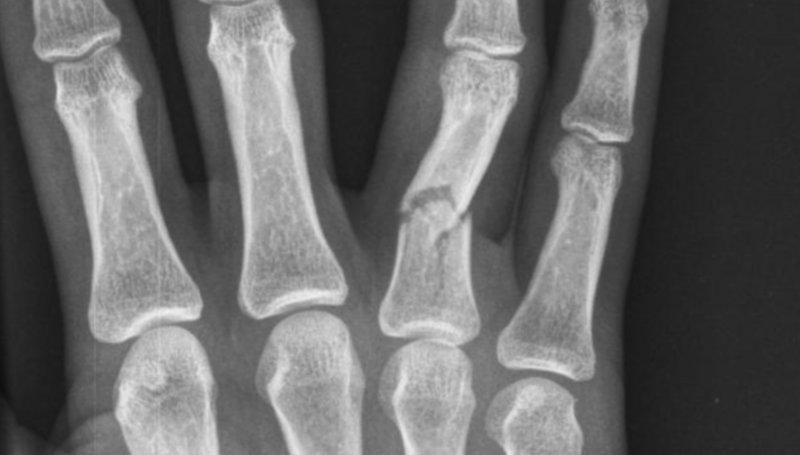

Poškodbe rok sodijo med najpogostejše poškodbe. Odprte poškodbe, kjer je prisotna rana na koži so nevarnejše od zaprtih, saj je rana vstopno mesto za bakterije, ki lahko povzročijo vnetje. Pri vreznih in vbodnih ranah, velikost rane na koži običajno ni sorazmerna s poškodbo globje ležečih struktur. Zmečkanine in raztrganine nastanejo zaradi delovanja večjih sil in pogosto so prisotne vrzeli tkiv, ki jih je potrebno nadomestiti. Amputacija pomeni, da je del telesa v celoti ločen od amputacijskega krna.